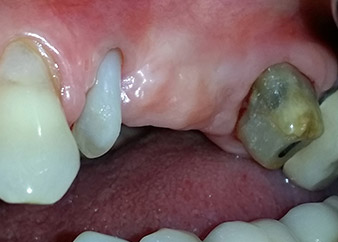

Risultati intermedi dopo due mesi

Le figure 17 e 18 mostrano il risultato clinico due mesi dopo l'intervento chirurgico. Il dente 24 mostra mobilità ridotta di classe 1 secondo Miller e i tessuti molli sono privi di infiammazione. A questo punto l'utilizzo della sonda è stato evitato per impedire una nuova infezione e per non disturbare l'attacco epiteliale. Era stata programmata una visita di controllo al rientro e il posizionamento dei perni di guarigione sei mesi dopo l'inserimento degli impianti.

Due mesi dopo l'intervento chirurgico il paziente non lamentava dolore.

Fig. 17: Due mesi dopo l'intervento chirurgico, il paziente non lamentava dolore e l'area non presentava infiammazione.

dopo l'intervento chirurgico

Fig. 18: Il dente 24 ora mostrava minore mobilità.

Nel caso presente si è proceduto a combinare il trattamento di una lesione endoperiodontale con il posizionamento di impianti e contemporaneamente il rialzo del seno mascellare, e procedure GBR e GTR nella mascella sinistra posteriore. Poiché entrambi i denti di appoggio per il ponte 24-27 presentavano una prognosi negativa, il trattamento odontoiatrico è stato eseguito solamente per soddisfare il desiderio della paziente di conservare i propri denti. Inoltre, poiché la paziente non accettava una protesi rimovibile provvisoria, il ponte è stato ricementato in vista del periodo di osteointegrazione degli impianti sommersi 25 e 26.

Prognosi e opzioni di ricostruzione

Durante la visita prevista due mesi dopo l'intervento chirurgico, la mobilità del restante "elemento dentale" 24 si era già ridotta dalla classe 2 secondo Miller alla classe 1. L'attacco del tessuto molle era a livello del vicino dente 23. Inoltre, la paziente non presentava sintomi endodontici o periodontali, quindi la prognosi è stata rivista.

Tuttavia, poiché la maggior parte del tessuto osseo buccale e prossimale è mancante e il materiale composito di ricostruzione si estende fino alla sezione apicale della radice, per ragioni biologiche non è possibile attendersi un livello di riattacco più elevato (Sculean et al., 2008).